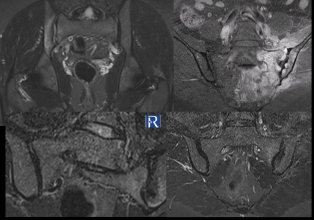

Case 1 Clinical presentation: A 36-year-old man presenting with right hip pain. The patient is HLA-B27 positive. MRI findings: MRI demonstrate ...